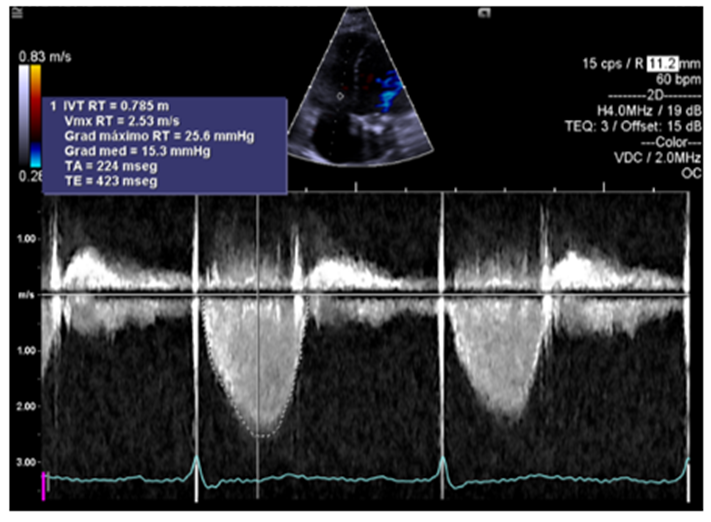

The second case is a course of worse prognosis of aA 47-year-old female patient with a family history of a deceased brother due to heart failure and a living sister with the same clinical syndrome who has currently undergone a transplant. She had a cardiovascular history of mitral valve replacement in 2016 and is currently undergoing treatment for heart failure. She attended the cardiology consultation for the first time due to dyspnea when climbing stairs that had been developing for six months. She denied DPN or orthopnea. Cardiovascular physical examination revealed rhythmic heart sounds of adequate intensity. S1 and S2 were unchanged, and S3 or S4 showed a prosthetic click in the mitral valve focus of adequate intensity, with no additional acoustic phenomena, and no pleuropulmonary syndrome. As part of the protocol, diagnostic aids were requested. A chest x-ray showed a mitral valve prosthesis in position, grade II cardiomegaly, and an electrocardiogram showed complete right bundle branch block. A transthoracic echocardiogram showed a dilated left ventricle with a 57mm end-diastolic diameter and 44mm end-systolic diameter, with a normofunctioning prosthesis with a mean gradient of 3.8 mmHg and an area of 1.5 cm2. A dilated left atrium had an indexed volume of 32 mm. Generalized hypokinesia, with reduced systolic function of 36%, and LVEF due to longitudinal global strain of 40%. Moderate secondary functional TR with an indexed ring of 37 mm. Treatment was started with loop diuretics, ACEIs, beta-blockers and VKAs. Due to family history, a genetic test was requested, which documented a mutation in the LMNA gene, on chromosome 1q22: c.568c> t (p.arg190trp), which allowed establishing the prognosis and prompt referral to the heart failure service with a path to heart transplant, however with progressive clinical presentation (persistence of dyspnea, NYHA functional class II and episodes of DPN), with a new echocardiogram two years later with respect to the initial one that reported dilated cardiomyopathy with reduced biventricular function, normofunctional mechanical mitral prosthesis, LVEF of 25% by biplane Simpson, right ventricle with dilated diameters, severe tricuspid regurgitation secondary to annulus dilation. Heart failure treatment was adjusted by adding complete neurohumoral blockade, with sequential dose adjustment, electrocardiogram in sinus rhythm QRS 140 ms RBBB morphology, ergospirometry was requested to objectively determine functional class, patient with MAGGIC prognosis of 10 points, mortality at 1 year of 3.9% and at 3 years of 10.2, with rapid progression of the disease despite complete treatment of heart failure for which the patient was taken to ICD for prevention of sudden cardiac death, currently undergoing heart transplantation.

Figure 4: Continuous Doppler in the tricuspid valve showing the regurgitation spectrum.